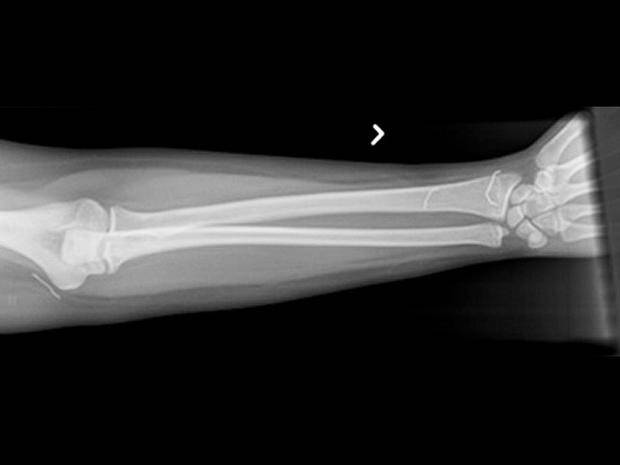

Samookaleczenia są niebezpieczne – oprócz ryzyka wywołania infekcji, umieszczanie w ciele przedmiotów może uszkodzić nerwy lub naczynia krwionośne. – W skrajnych przypadkach oprócz krwawienia (w tym wewnętrznego) może wystąpić nawet udar – powiedział Shiels.

– Jeśli dasz niektórym z tych dzieciaków magazyn do poczytania, to odzyskasz go z brakującymi zszywkami – mówi Shils. – Daj im ołówek, a wyciągną grafit i wsadzą do pod skórę.